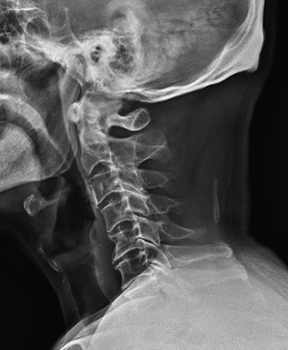

그래서 경추 X-ray를 찍어봤는데...

역시나였습니다 ㅠㅠ

목뼈가 문제였어요.

그림14.png

<Fig 1. 경추 X-Ray>

원래 목뼈는 C자 곡선을 이루어야 정상이에요.

이 곡선이 충격을 흡수하고, 머리 무게를 효율적으로 지탱해주거든요.

근데 이분의 목은 곧게 펴져 있었어요.

거기다 퇴행성 변화까지 심했고요.

'아, 이래서 머리가 어지럽고 멍했구나...'

경추의 변형이나 디스크 탈출, 협착 같은 게 생기면

신경이 자극을 받게 되는데요.

그러면 그 신경이 분포하는 부위에 통증과 어지럼증이 퍼져요.

후두부는 물론이고, 이마, 귀, 턱, 심지어 눈 주변까지도요.

이걸 우리는 '경추성 어지럼증'이라고 부릅니다.

게다가 목 주변 근육이 과긴장되면서 혈류 장애까지 생기니까

머리가 멍한 느낌, 머리가 띵한 증상이 더 심해지는 거죠.